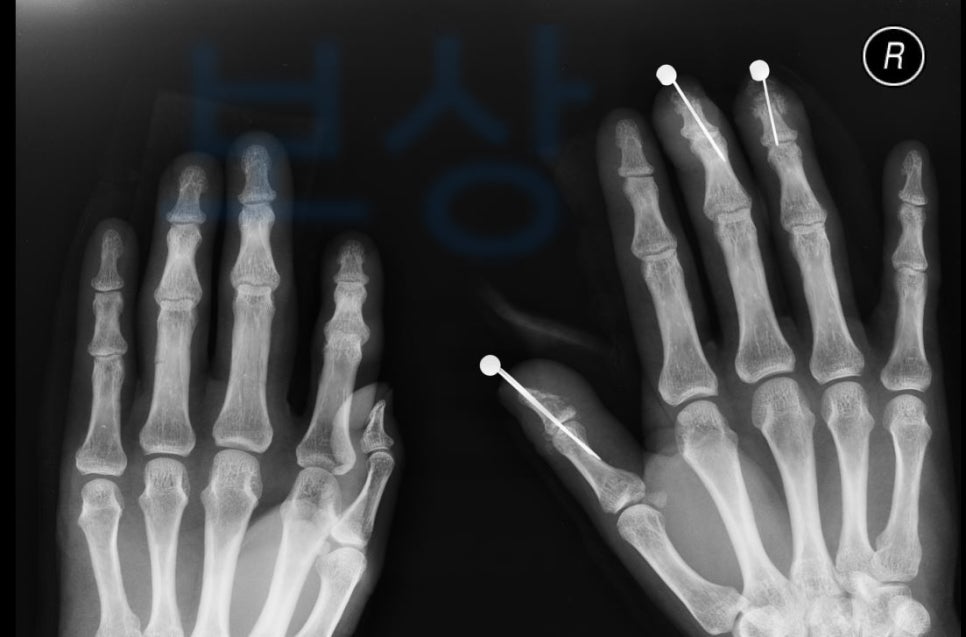

김@@님의 보상 사례 함께 보시며 내 사고와 비교해 보세요. 회사에서 일하시다 낙하물이 손에 떨어져 산업재해 사고를 당하셨습니다.

김@@님은 응급실 내원하여 정밀 검사를 받으셨고 손가락골절수술 시행하게 되었죠.

양손에 낙하물이 떨어져 압궤 손상 진단을 닿았고 양손 다 골절 및 힘줄 손상에 혈관도 손상되었습니다. 진단코드는 s678 및 s6253, s6262, s6264, s6558, s6688 김@@님은 손가락골절수술 후 재활치료를 받고 계셨는데요,

그 결과 최근 생손보 약관 상으로 **엄지손가락의 뚜렷한 장해 10% **와 옛날 생명보험 급수 장해는 6급에 해당되었습니다. 보상 파트너는 평가된 장해 진단을 기초로 손해사정서와 증빙자료를 각 보험사에 송부하였습니다.